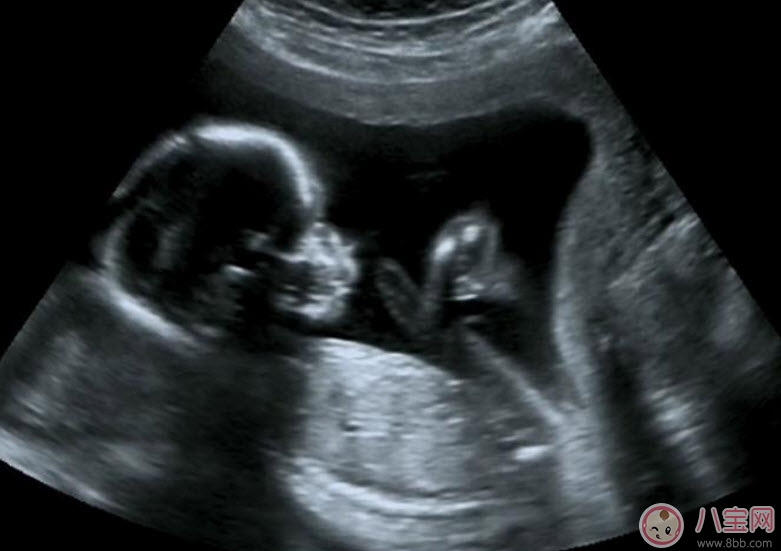

B超能夠直觀胎兒在母體內(nèi)的活動(dòng)狀況,諸如呼吸情況、胎兒的運(yùn)動(dòng)、整個(gè)身體大的運(yùn)動(dòng)、肢體的運(yùn)動(dòng)、胎兒的吞咽動(dòng)作等等,可以一覽無(wú)余。之外,通過(guò)觀察胎兒的張力是否良好,可以判斷胎兒在宮內(nèi)是否缺氧或者受到損害,準(zhǔn)確預(yù)報(bào)胎兒安危。